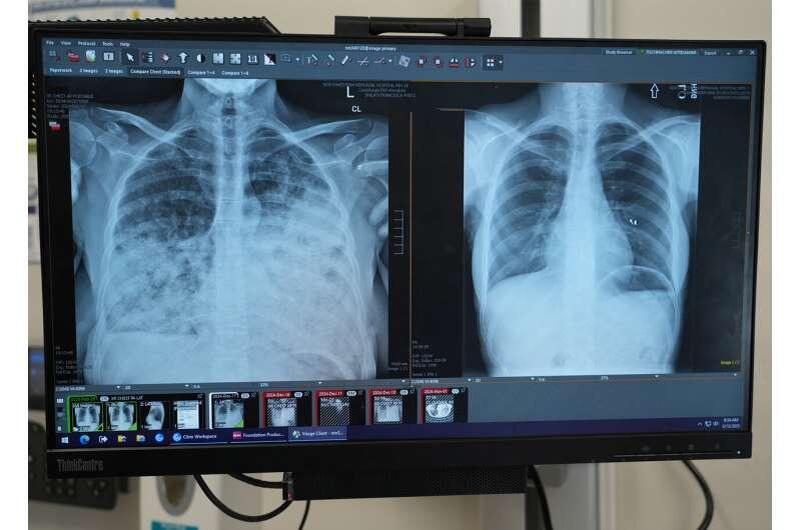

Скрининг рака лёгких не работает для большинства пациентов, показало новое исследование

Новое исследование специалистов Северо-Западной медицины (Northwestern Medicine) выявило тревожную тенденцию: из почти тысячи подряд пациентов с диагностированным раком лёгких только 35% соответствовали текущим критериям скрининга Службы профилактики США (USPSTF).

Остальные — две трети! — никогда бы не попали на профилактическое обследование.

Исследование, опубликованное в журнале «JAMA Network Open», предлагает пересмотреть сам подход.

Универсальный возрастной скрининг: 40–85 лет

Учёные рассчитали: если перейти к диагностике исключительно по возрасту, от 40 до 85 лет, без учёта курительного стажа, можно выявлять до 94% случаев рака лёгких.